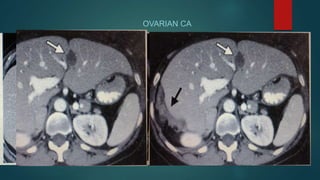

OVARIAN CA